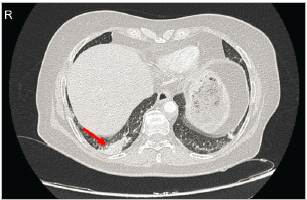

Se realizaron tomografías contrastadas (TC) en tórax y abdomen. El estudio de tórax mostró asimetría al realce del parénquima basal derecho y área de hipoperfusión hacia el aspecto medial de atelectasia ipsilateral, concluyente con TEP agudo en arteria segmentaria basal posterior derecha con aparente infarto basal posterior ipsilateral (Figura 2).

Figura 2 Corte axial de TC torácico contrastado, evidenciando área de hipoperfusión basal derecha (flecha blanca), concluyente para TEP agudo de arteria segmentaria basal posterior derecha con aparente infarto basal posterior derecho.